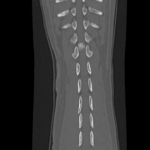

椎間板ヘルニア

ミニチュアダックスフントが急に後肢麻痺を発症したとのことで治療依頼がありました。

椎間板ヘルニアはダックスに多い疾患であり、若齢でも発症します。脊髄圧迫の程度が軽ければ内科治療でも対応可能ですが、重度の圧迫があると早期の手術が勧められます。

この患者さんはMRI撮影後、すぐに手術を行いました。症状が重いため回復には時間がかかると思いますが、病院・家でリハビリを行って自力歩行を目指します。